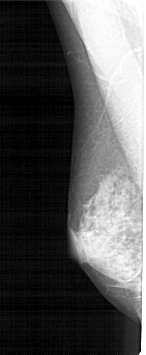

A_1867_1.LEFT_MLO

LEFT_MLO LINES 5311 PIXELS_PER_LINE 2176 BITS_PER_PIXEL 12 RESOLUTION 43.5 NON_OVERLAY